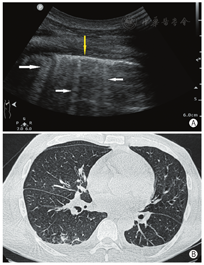

肺实变:肺组织完全失气化后表现为实性组织回声,呈大小不等的斑片状或者"肝样变",可伴有"支气管充气征"或者"支气管充液征"(图9)。

胸腔积液:超声表现为胸膜腔内低/无回声区,可见条索样分隔,脓胸时应注意与实变的肺组织鉴别(图10)。

横向扫查图像测量病灶最大左右径和最大前后径,纵向扫查图像测量病灶最大上下径。

测量最大深度(具体测量方法见图10下方注释)。

少量:平卧位时液体深度小于2 cm或坐位时液体平面局限于肋膈角(积液量小于500 ml)。

中量:平卧位时液体深度为2~4 cm或者坐位时液平面位于膈顶至第6肋间(积液量约500~1 000 ml)。

大量:平卧位时液体宽度大于4 cm或者坐位时液平面高于第6肋间(积液量大于1 000 ml)。